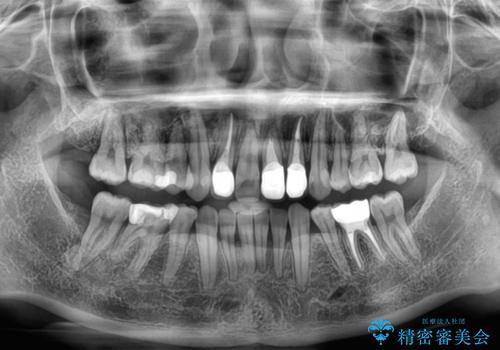

- 前歯のデコボコと、その結果むし歯が進行していることを気にして来院された患者様です。

前歯や奥歯の根管治療を行い、その後上下左右の第一小臼歯4本を抜歯してワイヤー装置にて矯正治療を行うこととしました。

矯正治療後には、根管治療を行った歯をオールセラミッククラウンにて補綴治療を行うこととしました。